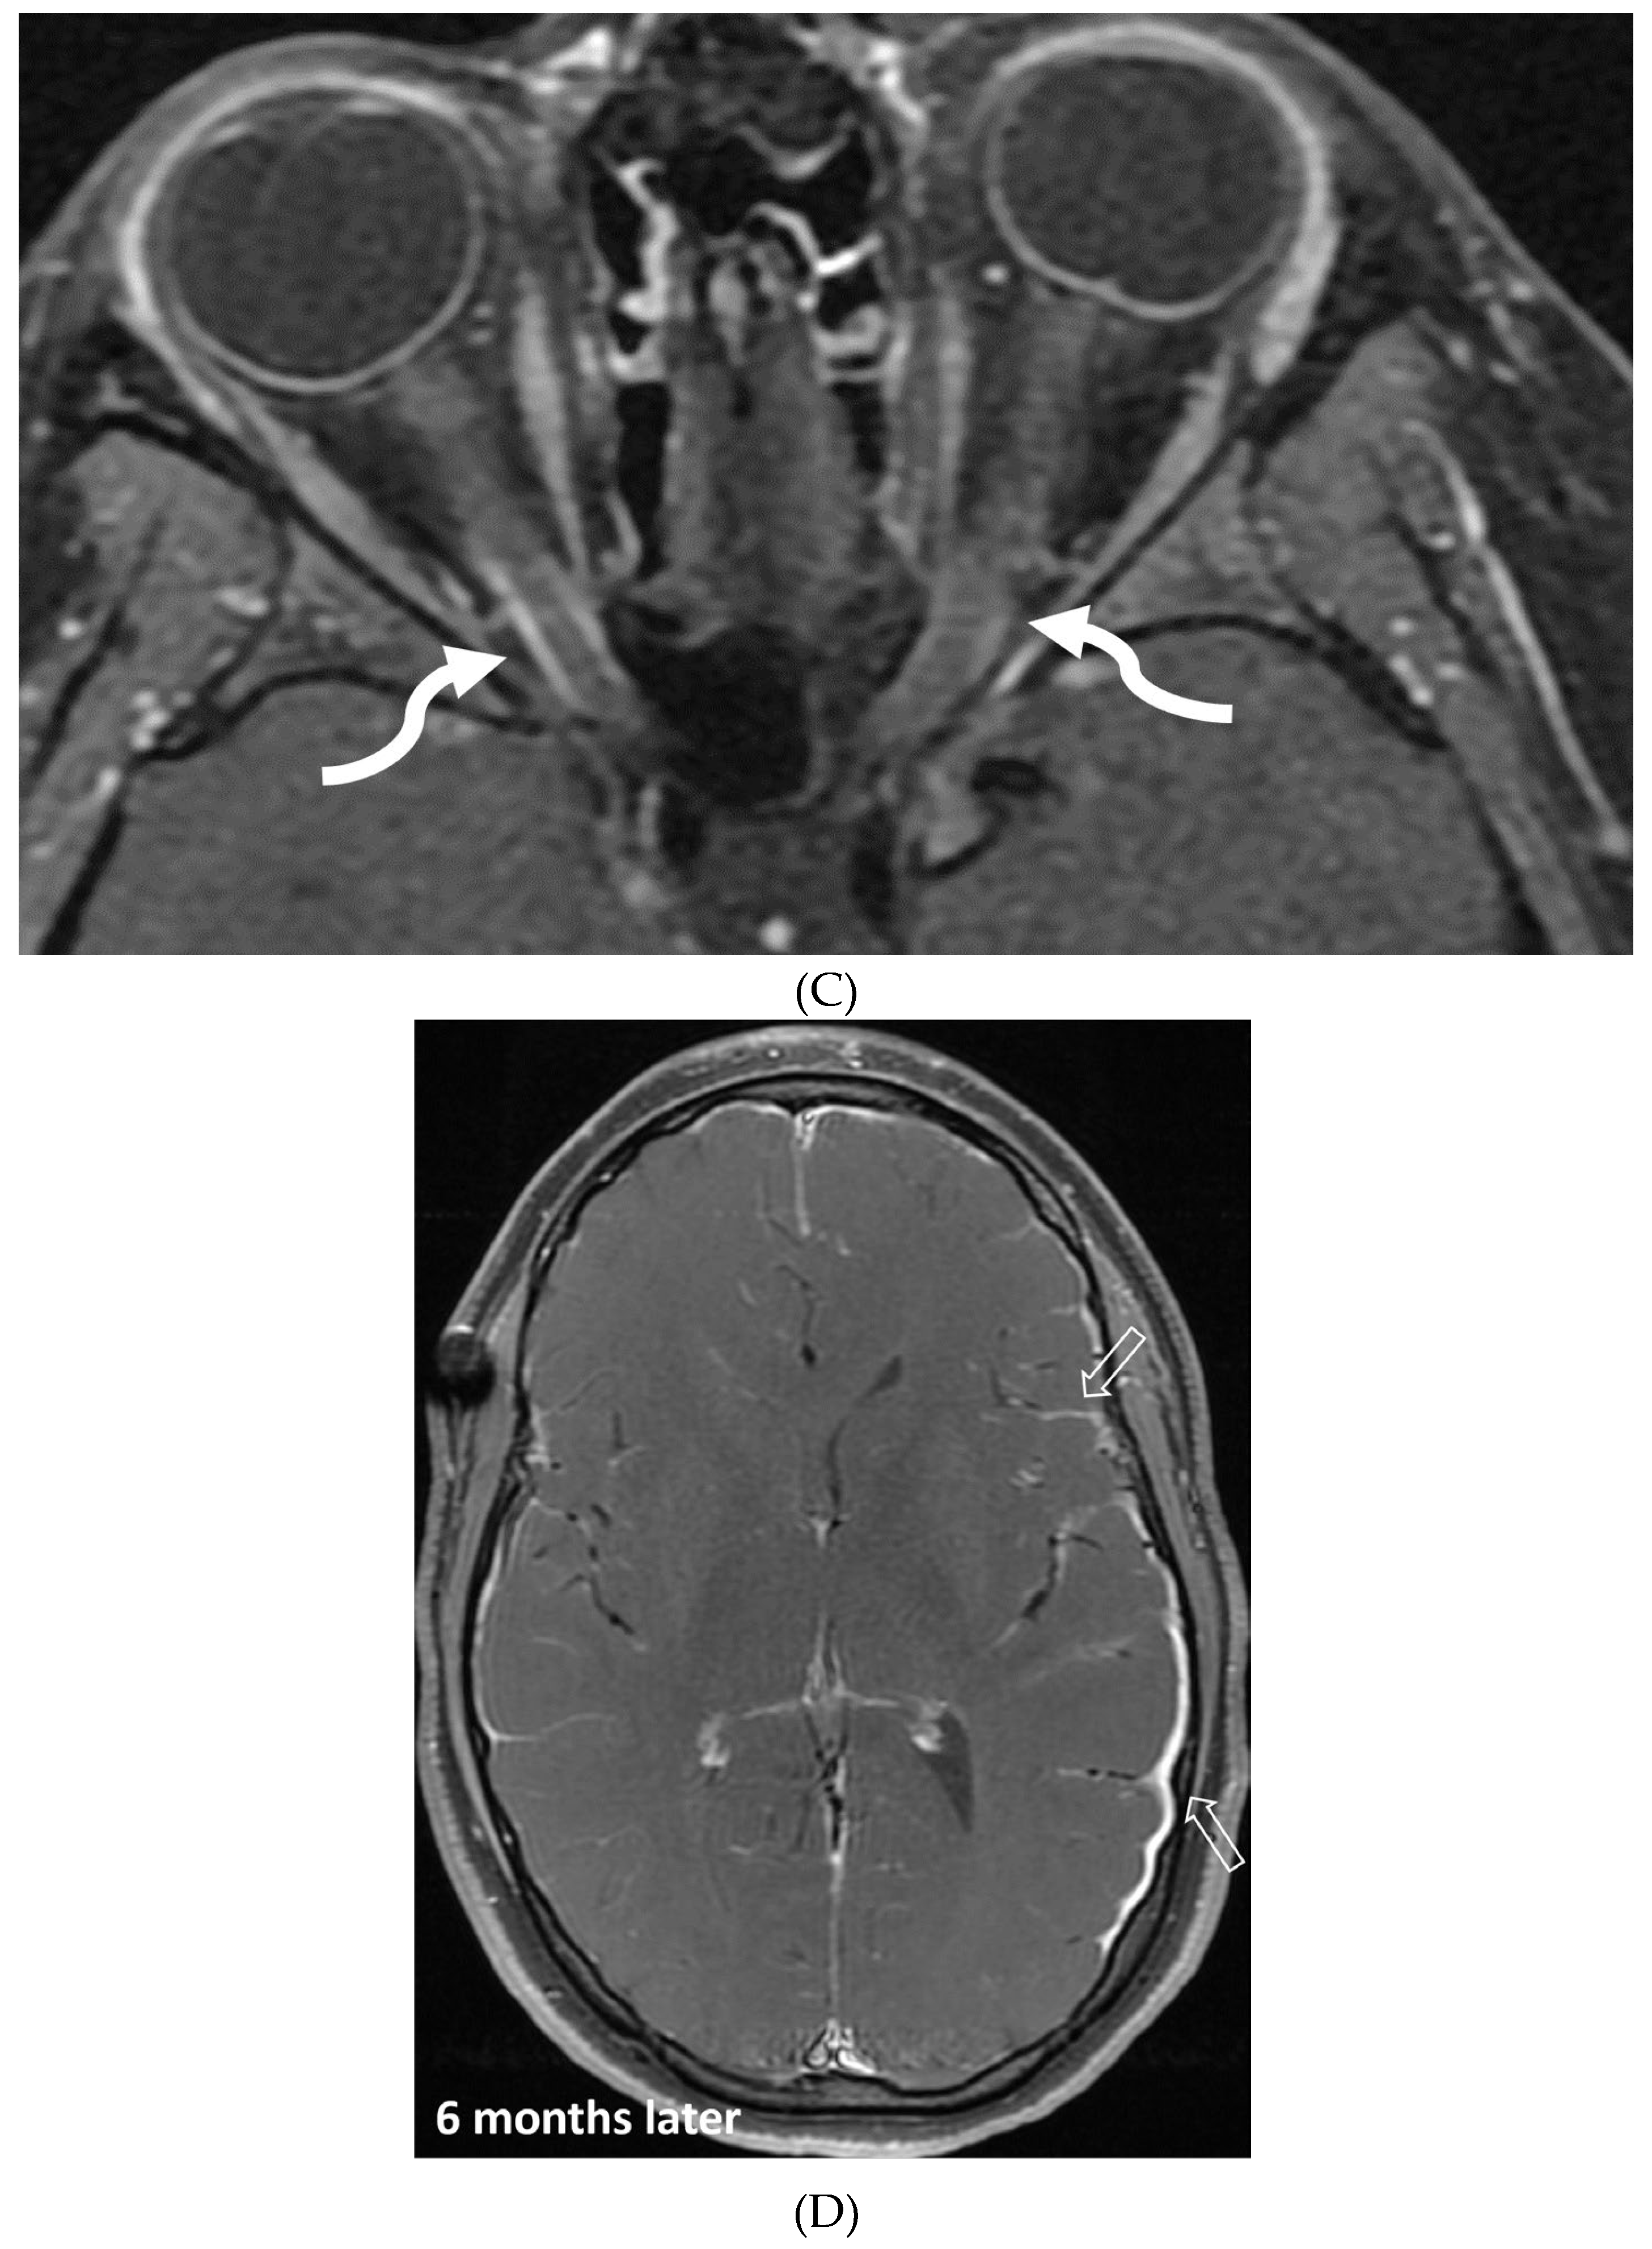

- Li L, Liu W, Cai Q, Liu Y, Hu W, Zuo Z, Ma Q, He S, Jin K. Leptomeningeal enhancement of myelin oligodendrocyte glycoprotein antibody-associated encephalitis: uncovering novel markers on contrast-enhanced fluid-attenuated inversion recovery images. Front Immunol. 2023 Jun 20;14:1152235. PMID: 37409120; PMCID: PMC10318903. [CrossRef]

- Shahriari M, Sotirchos ES, Newsome SD, Yousem DM. MOGAD: How It Differs From and Resembles Other Neuroinflammatory Disorders. AJR Am J Roentgenol. 2021 Apr;216(4):1031-1039. Epub 2021 Feb 17. PMID: 32755221. [CrossRef]

- Gadde JA, Wolf DS, Keller S, Gombolay GY. Rate of Leptomeningeal Enhancement in Pediatric Myelin Oligodendrocyte Glycoprotein Antibody-Associated Encephalomyelitis. J Child Neurol. 2021 Oct;36(11):1042-1046. PMID: 34547933; PMCID: PMC9054459. [CrossRef]

- Valencia-Sanchez C, Guo Y, Krecke KN et al. Cerebral Cortical Encephalitis in Myelin Oligodendrocyte Glycoprotein Antibody-Associated Disease. Ann Neurol. 2023 Feb;93(2):297-302. Epub 2022 Dec 2. PMID: 36372941; PMCID: PMC10107670. [CrossRef]